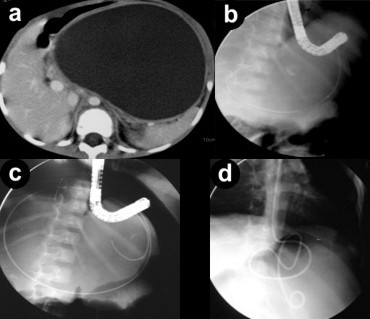

Four patients had a single pseudocyst and three patients had multiple pseudocysts. The size of pseudocysts ranged from 4 to 14 cm and none of the pseudocysts had significant necrotic debris on MRI. These patients presented 4 to 12 weeks after the abdominal trauma. Two patients with single pseudocyst had a bulge in the stomach and were treated with transmural drainage (Figure 1). There were no complications of the procedure and the pseudocysts resolved with cessation of nasocystic drain output in both the patients in 4 and 5 weeks, respectively. Post-resolution ERCP documented complete and partial disruption of the main duct in the head region in one patient each. A 5-Fr bridging stent was placed in patient with partial disruption and repeat ERCP after 4 weeks documented healing of the disruption. Thereafter, the transmural stents as well as the transpapillary stent was removed. Transmural stents have not been removed in patient with complete disruption. There has been no recurrence of symptoms or the pseudocysts in both these patients over a follow-up of 20 and 16 months.

Figure 1. a. Large post-traumatic pseudocyst. b. Guide wire pushed into pseudocyst after puncturing with needle knife. c. Guide wire coiled into the pseudocyst. d. A 7-Fr nasocystic drain placed. |